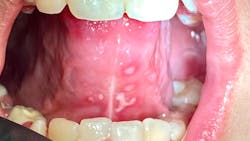

Note: The pictures are not of the highest quality as the patient was in extreme discomfort when I took them.

Definitive diagnosis is likely one of two: Herpangina or acute primary herpetic gingivostomatitis

The saying “nothing is for certain unless it’s in a petri dish” stands true in all pathology cases, including this one. However, based on the symptoms and clinical presentation, I was able to surmise that it was more than likely either herpangina or APHG, although I’m leaning toward APHG.